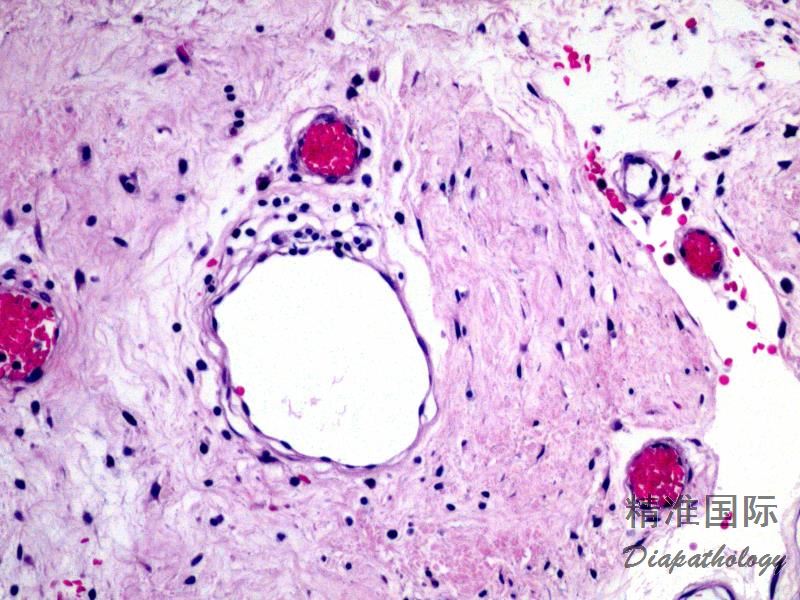

- 组织学上边界清楚,呈叶状、细胞稀疏性病变伴显著黏液样基质,温和短梭状至星状细胞伴泡状胞核,薄壁状血管,核分裂罕见,常见炎细胞浸润(尤其中性粒细胞的存在可帮助其与其他黏液病变鉴别)。皮肤黏液瘤中常见囊状扩张的毛囊结构。组织学形态类似于其他部位的黏液瘤。